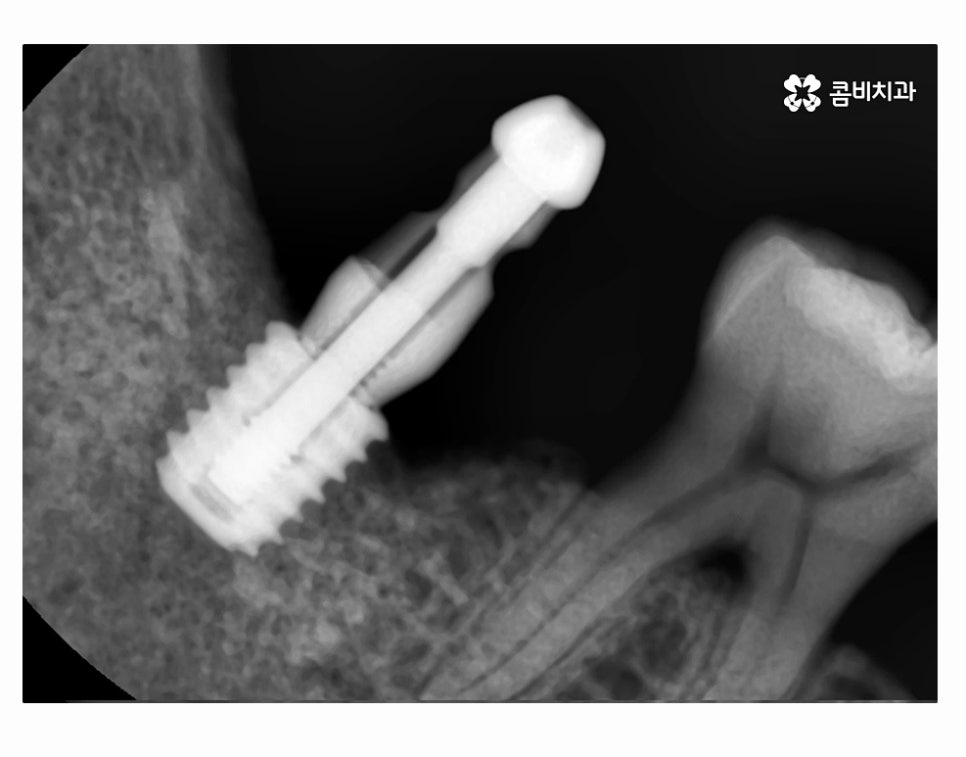

잇몸질환이 치아의 뿌리 염증까지 이어져서 어금니 발치까지

이어진 사례의 경우에는 발치 후 잇몸질환의 회복과

잇몸 뼈가 건강하게 차오르도록 각별한 주의를 기울여야 하며

필요한 경우에는 뼈이식을 진행해야 할 수 있어요.

충치나 사고로 인해서 치아를 잃게 되는 경우에는

발치 후 즉시 식립 방식으로 임플란트를 식립하여 치료 기간이

일반적인 시술 방법에 비해서 단축 가능한 경우도 많지만

치아 뿌리 염증이 잇몸질환으로 인해 발생한 경우에는

발치와 잇몸 뼈의 회복, 뼈이식 등의 과정이 필요할 수 있으며

개인별 건강 상태도 충분히 잘 고려해야 하기 때문에

빠른 치료보다는 안전하고 건강하게 시술하는 것이 관건이라고 볼 수 있어요.